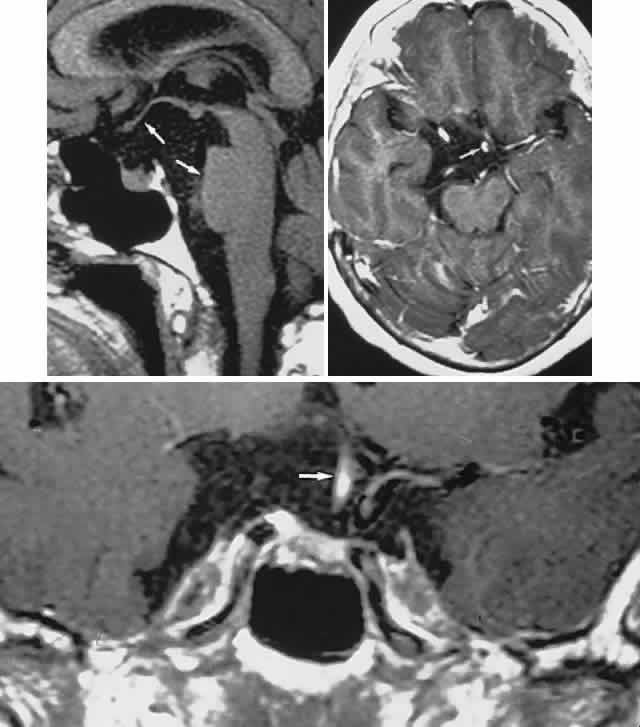

Fig. 3. Neuroimaging of pituitary adenomas. A. Axial computed tomography (CT) section shows a round tumor mass filling the suprasellar cistern; ring enhancement (arrows) indicates subcapsular hemorrhage. B. Contrast-enhanced coronal CT section through a large invasive adenoma. Note encasement of the carotid artery (arrows) and the position of the middle cerebral artery above (arrowheads). C. Axial CT section shows lateral expansion into the cavernous sinuses (white arrows) and a necrotic cyst (black arrow). D. Subfrontal superior extent of the mass. Note the middle cerebral arteries. E. Magnetic resonance imaging of a large lobulated prolactinoma, with suprasellar extension. Note the distortion of the third ventricle (open arrows) and extension toward the temporal lobe (long arrow); the tumor has not involved the sphenoidal sinus (s). F. Chiasm (arrowheads) is draped on the superior surface of the tumor (TR, 550 milliseconds; TE, 26 milliseconds). G. Sagittal section shows suprasellar growth with the chiasm above (arrowheads); the sella (arrows) and sphenoidal sinus (s) are normal (TR, 850 milliseconds; TE, 26 milliseconds). H. Hyperintense signal (TR, 2000 milliseconds; TE, 60 milliseconds) indicates the partial cystic character. Sagittal (I) and axial (J) sections with head tilt to the right, in case of a large cystic adenoma with an interface level between newer blood (white arrow) and older blood (black arrow) (TR, 800 milliseconds; TE, 30 milliseconds). K. Signal difference is intensified (TR, 2100 milliseconds; TE, 80 milliseconds). L. Hemorrhage (bright signal, arrow) in a pituitary adenoma with headache and bitemporal field depressions. M. Without interventions, 2-month follow-up showed spontaneous involution, with normal pituitary gland (arrow), stalk, and chiasm.